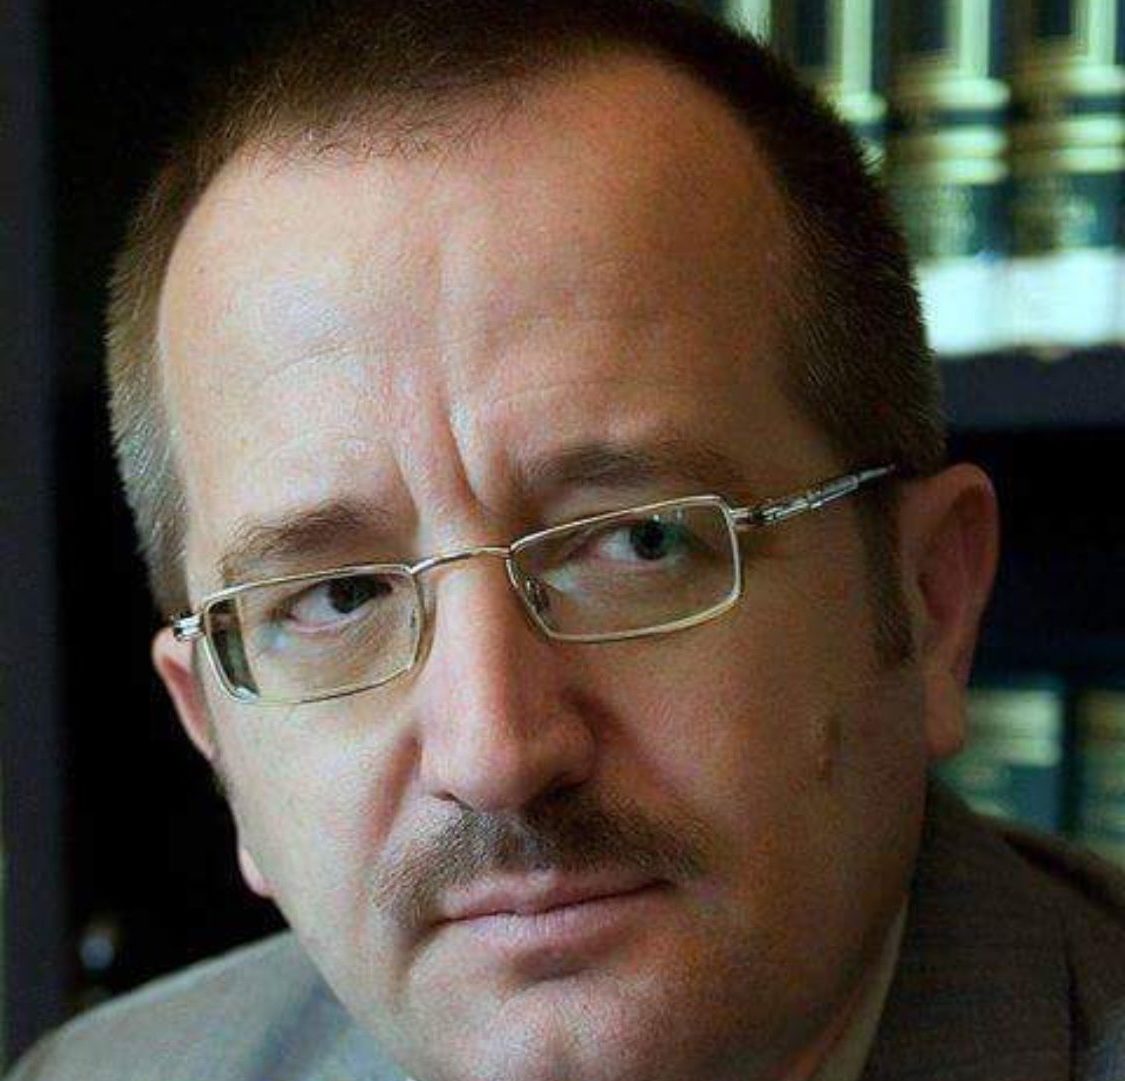

9 nga 10 raste mund të ishin parandaluar me testimin dhe trajtimin në kohë gjatë shtatzënisë, tha Laura Bachmann, shefe mjekësore në Divizionin e Parandalimit të STD të CDC.

Duke i trajtuar shpejt pacientët, profesionistët e kujdesit shëndetësor mund të zvogëlojnë disa nga pengesat më të mëdha për kujdesin që disa nëna kanë nevojë, tha Bachmann.